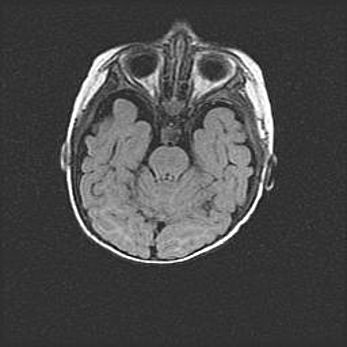

Наружная гидроцефалия с возможной атрофией височных областей.

Возраст: 28 дней

Вес: 3670 г

Пол: мужской

Окружность головы: 38 см

Срок гестации: 40 недель

Гидроцефалия головного мозга у новорожденных – это заболевание, которое характеризуется скоплением избыточного количества спинномозговой жидкости в желудочковой системе головного мозга в результате затруднения её перемещения от места выработки к месту поглощения в кровеносную систему или вследствие нарушения абсорбции. При открытой наружной форме гидроцефалии у новорожденных расширяются и переполняются субарахноидные пространства.

При нормотензивных  формах,  которые,  как  правило,  являются  следствием  перенесенных ишемических  повреждений  паренхимы  мозга,  возможно  сочетание микроцефалии  с нормотензивной гидроцефалией. В основе данных изменений лежит атрофия больших полушарий с преимущественной  локализацией  в  лобно-височных  областях.